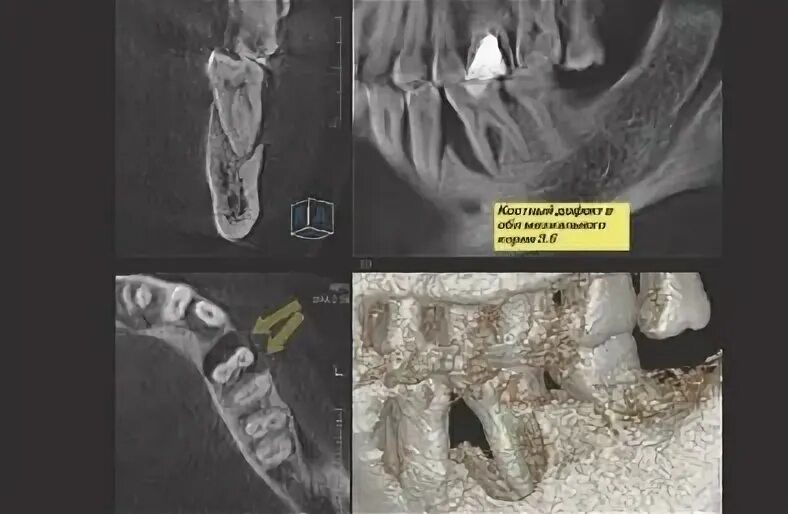

Picasso кт